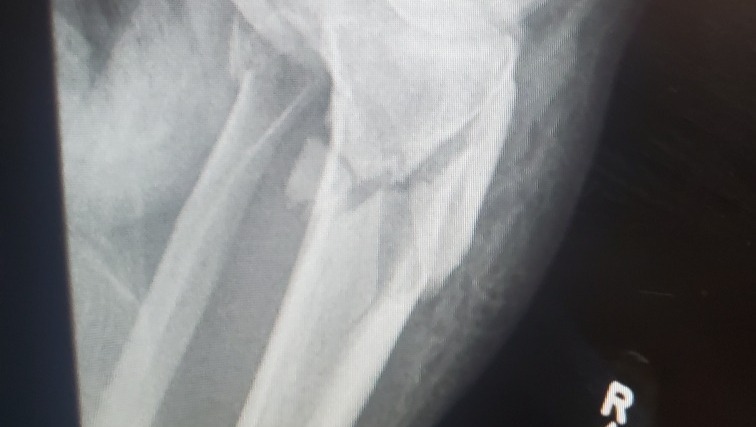

This is one of those “traumatic events that change your life.” Before this even I had never broken a bone or gone through any type of surgery. The diagnosis was “closed displaced comminuted plateau fracture of shaft of right tibia and closed transverse fibula fracture.” The surgeon said, "it's the worst fracture he has seen in his 17 years of being a doctor."

They got me as close to the Ranger vehicle as possible and helped me stand on one leg and I hopped into the passenger seat. The Ranger vehicle then took me down the access road to where the ambulance was, and I hopped to the gurney. Good thing was the hospital was less than 5 minutes from where we were riding. The ER nurse was really nice and tried to save as much clothes and bike gear as possible. She also made sure we had everything we needed. There was a bet with the EMTs that I had just dislocated my knee. They were wrong. From the X-rays, my tibia was shattered, and I also fractured the fibula. The break was an inch and a half below my knee.

Surgery was needed to reset the bones and straighten my leg. I was put into an external fixation where they screwed this device into my bones to help me keep the bones in place while the swelling went down in my leg. This device was only supposed to be on for two weeks. At the follow-up to schedule the second surgery, the swelling had not gone down enough to put the plates and screws that would replace the external fixation. I was lucky that the fracture was not an open one and I was lucky to keep my leg because of how close the break was to my knee and how serious the fracture was to both bones.